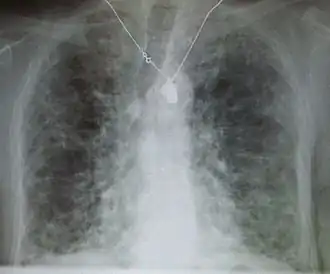

Рентгеновский снимок грудной клетки: фиброз легких, предположительно возникший вследствие приема амиодарона.

Причинами являются загрязнение окружающей среды, прием некоторых лекарств, заболевания соединительной ткани, инфекции и интерстициальные заболевания лёгких[1][3]. Наиболее распространён идиопатический лёгочный фиброз (ИЛФ) — интерстициальное заболевание лёгких неизвестной этиологии[1][3]. Диагноз может быть поставлен на основании симптомов, результатов медицинской визуализации, биопсии лёгких и исследование функции внешнего дыхания[1].